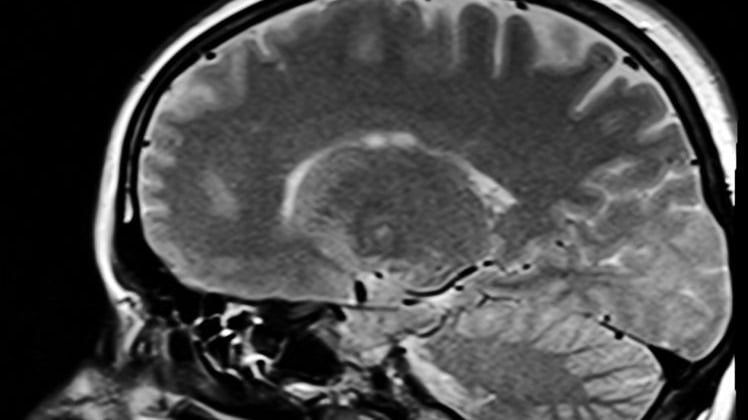

Medizinische Rätsel: Volles Bewusstsein trotz Hirnschäden

Von unerklärlichen Klarheitsmomenten Demenzkranker und von einem Mann, der mit nur 10% Gehirnmasse über ein ganz normales Bewusstsein verfügt